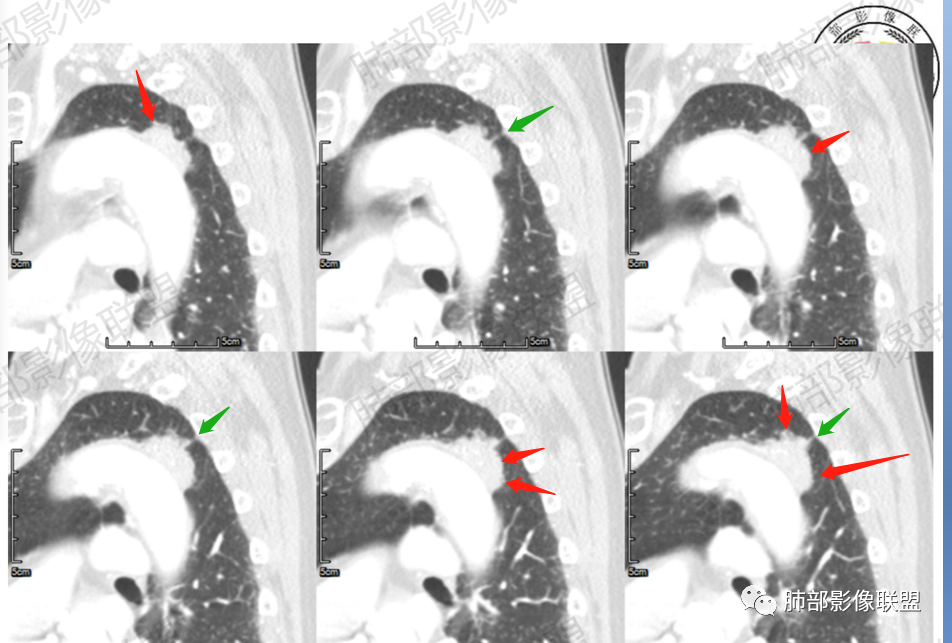

尘缘:病灶沿主动脉匍匐样生长,但整体明显膨隆,胸膜牵拉凹陷,局部有小喇叭口样改变。

尘缘:边界清楚的GGO。

尘缘:局部血管增粗,扭曲

尘缘:局部有淋巴管增粗,小叶间隔增厚,提示癌淋可能。

尘缘:最后就是强化,虽然是明显渐进性强化,要考虑炎性可能,但腺癌明显渐进性强化的并不少见。

2.轴位显示主动脉弓旁依势傍行弧形高密度影,隐约见尖后段支气管进入并截止。病灶边界较清楚,见血管结构及线性影与邻近肺组织相延伸。

3.病灶渐进性显著均匀强化!动脉期未见主动脉腔异常通道。

4.冠矢状位病灶于弓上部偏后局限性“贝雷帽”状突起,提示病灶有局部膨隆特点,且病灶上份及后份饰以边缘较清楚磨玻璃影。